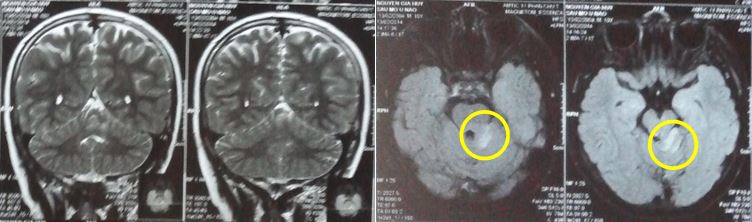

Trên phim chụp cộng hưởng từ (MRI) sọ não: thấy có khối tổn thương ở vị trí xung quanh củ xám, kích thước khối u 3,2 x 2,8cm, đồng tín hiệu trên T1, tăng tín hiệu T2, không ngấm thuốc sau tiêm.

Vì vậy bệnh nhân được xác định là có khối u Hamartoma (U mô thừa) ở vị trí quanh củ xám của não.

Hình ảnh MRI sọ não: Hình ảnh chụp cộng hưởng từ não của bệnh nhân

Chẩn đoán xác định: U mô thừa (Hamartoma) vị trí gần củ xám

Hình ảnh cộng hưởng sọ não từ trước điều trị: Kích thước khối u: 3,2 x 2,8cm

Chụp cộng hưởng từ có ý nghĩa chẩn đoán bệnh: trên xung T1 đồng tín hiệu, tăng tín hiệu trên T2, không ngấm thuốc.